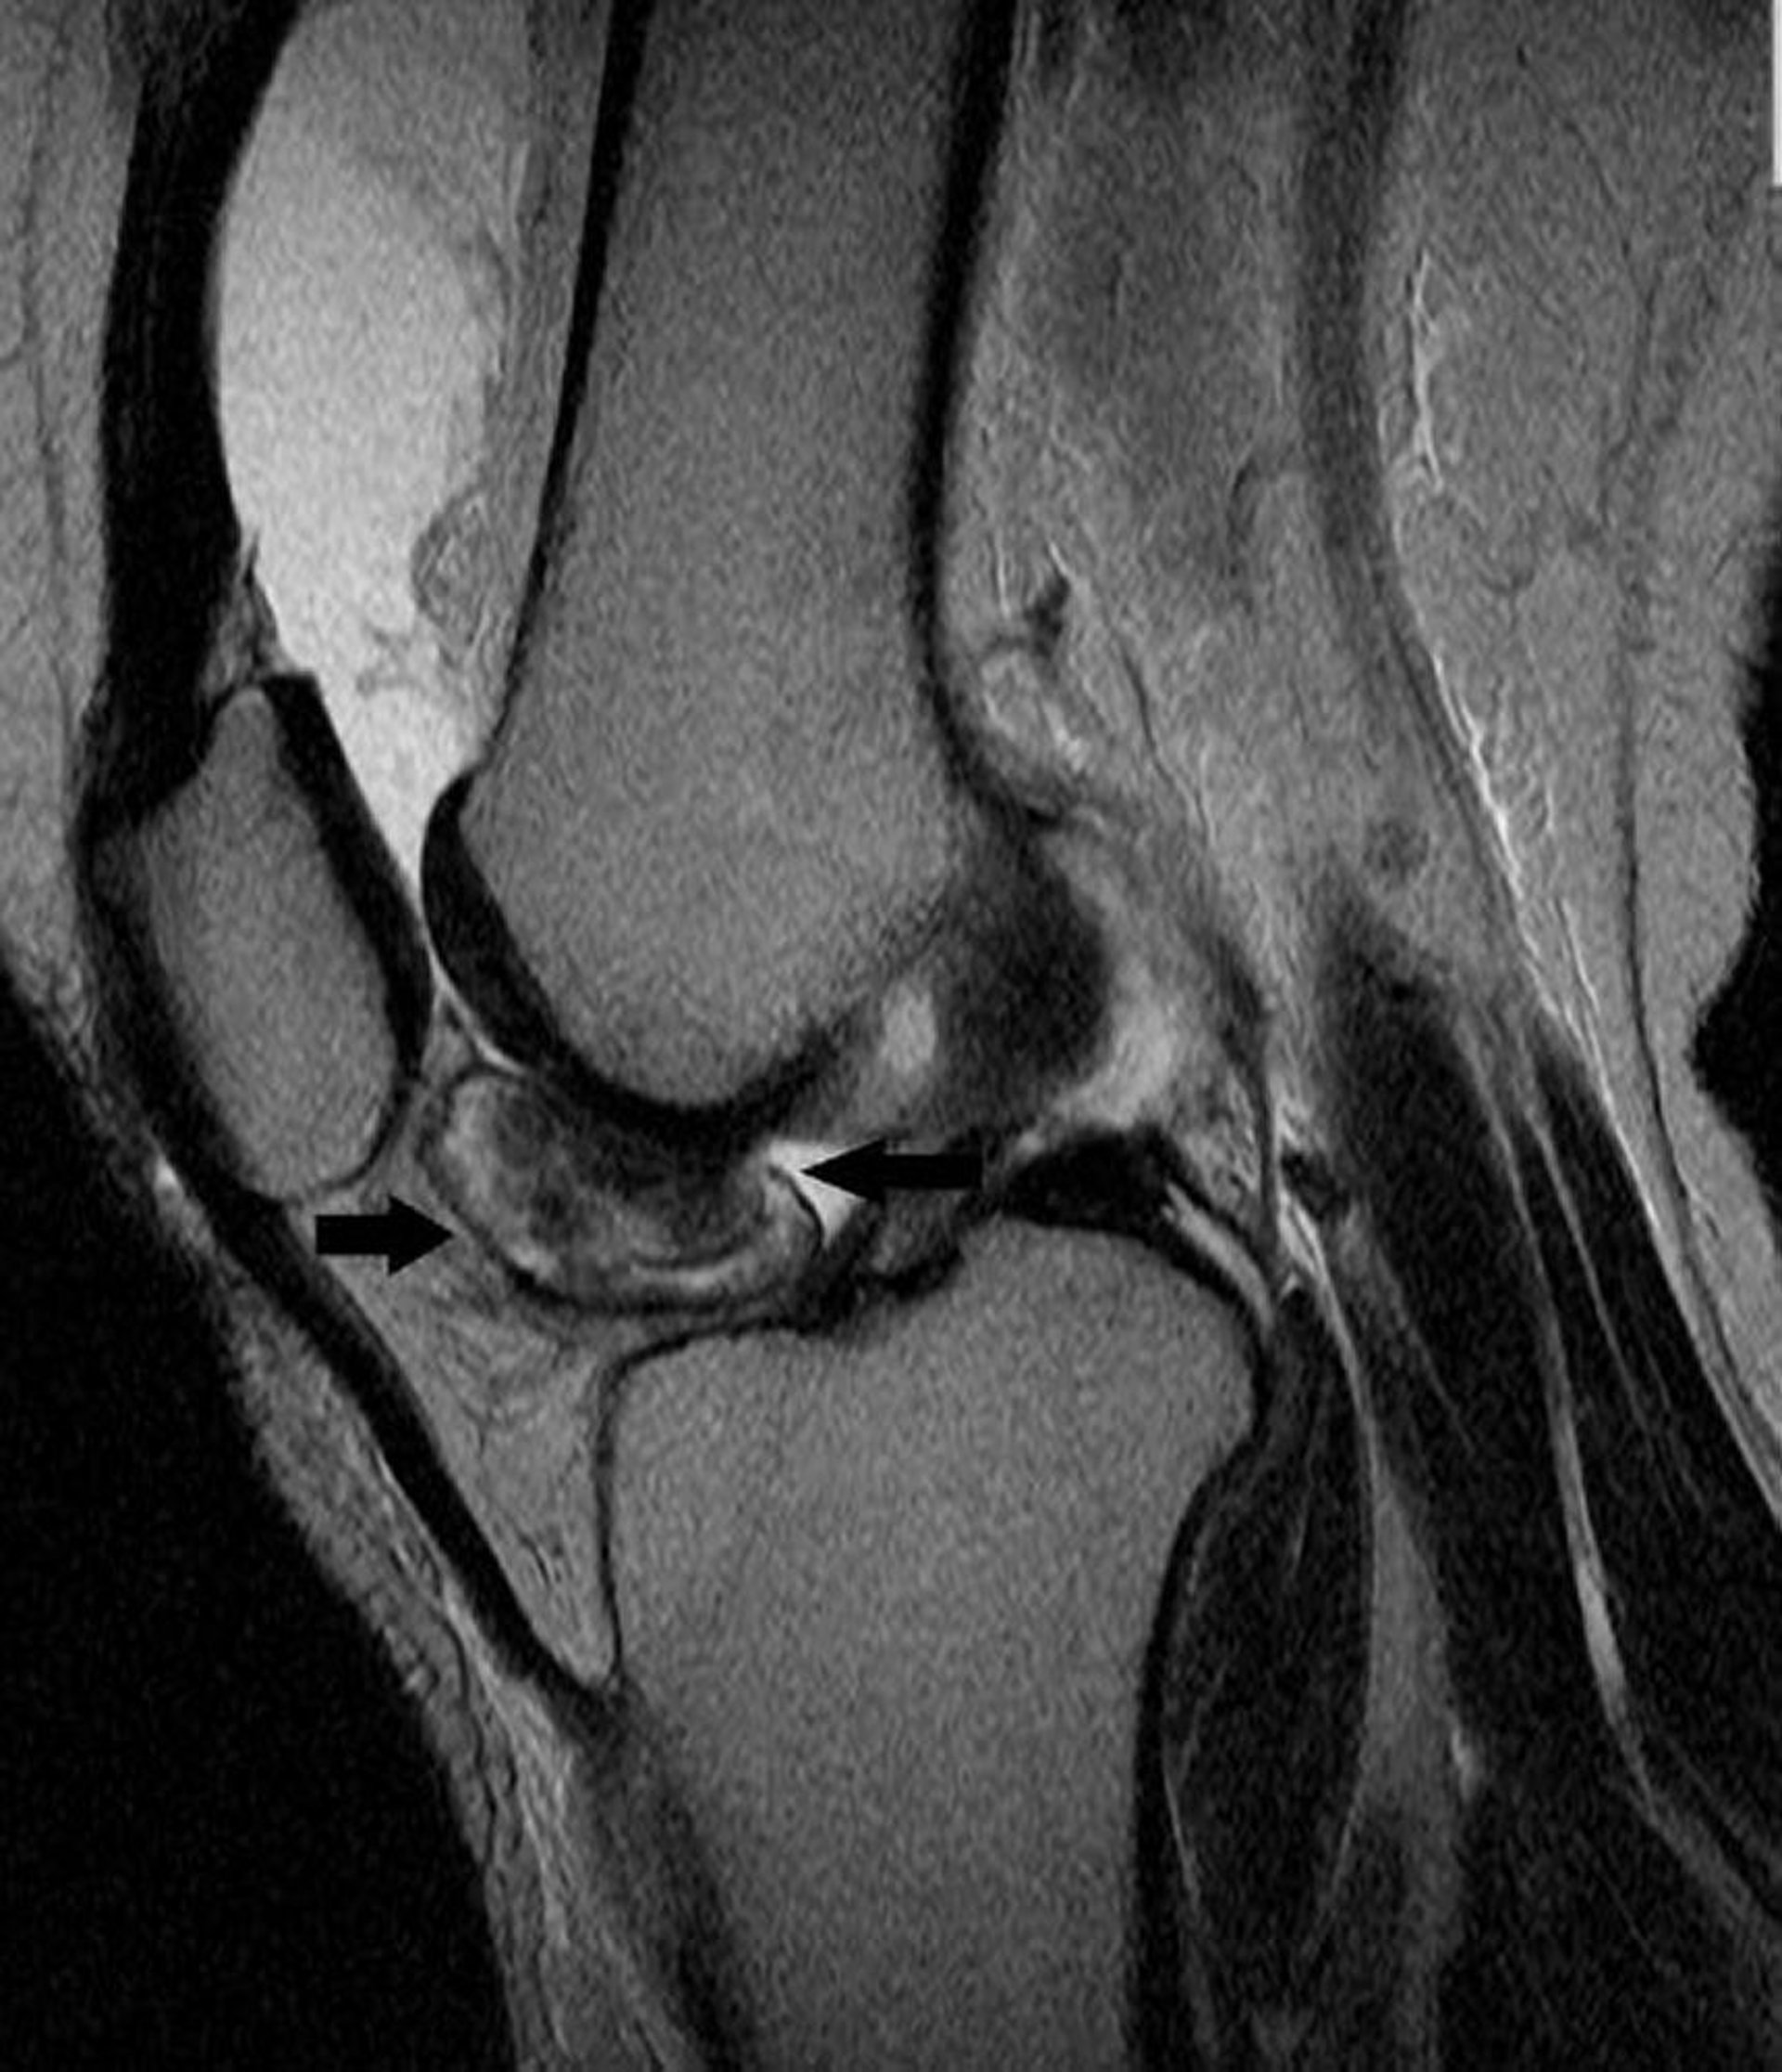

Esta RM de rodilla muestra un tumor de células gigantes tenosinoviales en el revestimiento de la articulación de la rodilla (flechas).

Image courtesy of Michael J. Joyce, MD, and Hakan Ilaslan, MD.